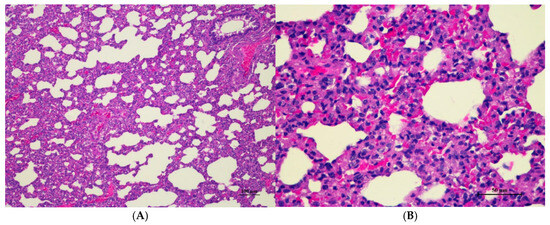

Figure 5.

Histopathological examination of rat lung tissue in acute toxicity from a single oral dose of CDF exhibited histopathological changes. (A) Lung tissue shows marked alveolar septa thickening with disrupted alveolar structure. Interstitial areas are expanded by cellular infiltrates (100×, H&E). (B) High magnification showed septal infiltration by mononuclear cells, hyperemia, and mild hemorrhage in alveolar space (400×, H&E).

Histopathological analysis revealed generally unremarkable findings in the liver, kidney, heart, and spleen, with only minor, scattered hepatocellular swelling and vacuolation in the liver, mild renal tubular degeneration in limited kidney areas, and focal myocardial vacuolation and lymphoid aggregation in the heart. Conversely, the lung exhibited significant pathological changes, characterized by alveolar septal thickening due to severe interstitial infiltration of lymphocytes and other mononuclear cells, nodular lymphoid aggregations, alveolar septal engorgement and hyperemia, alveolar edema, and multifocal mild alveolar hemorrhage, suggesting a potential site of inflammatory response.

Lung abnormalities in the lung tissue of both sexes were found, i.e., interstitial pneumonitis. The histopathologic features of the lungs show varying severity degrees of alveolar edema, alveolar septal engorgement, alveolar hemorrhage, and inflammatory cell infiltration to pulmonary parenchyma. In all groups, this abnormality may indicate infection from laboratory animals. However, further investigation is required. Cassava pulp dietary fiber was found to be well tolerated in a short-term toxicity assessment with non-toxic thresholds of 10.01 g/kg body weight/day for male rats and 11.21 g/kg body weight/day for female rats. Cassava pulp dietary fiber also showed cholesterol-lowering effects [4].